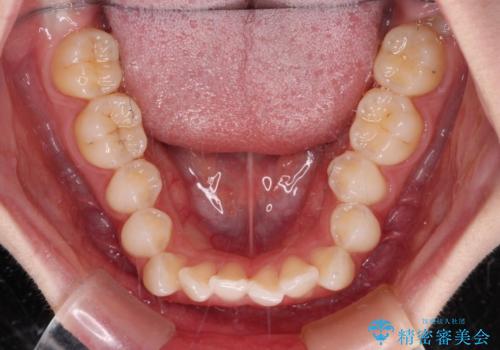

前歯のデコボコと深い咬み合わせ インビザラインできれいに改善

- 前歯のデコボコと下の前歯が隠れてしまう咬み合わせを気にして来院された患者様です。

インビザラインによる上下歯列の拡大と、IPR(歯と歯の間を削る)にるスペースの獲得により、口元のデコボコとディープバイトを改善することとしました。

インビザラインは、装着していない時間がどれだけ短いかが、治療期間を大きく左右します。こちらの患者様は1日22時間以上、毎日欠かさず装着してくださったため、1年弱という短期間で満足のいく歯列に整えることができました。